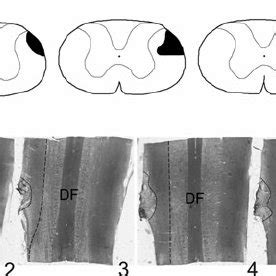

- Light Photomicrographs Showing Representative Sections Of... | Download ...